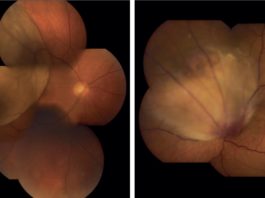

Retinografia wide-field nelle degenerazioni retiniche periferiche

La diagnosi precoce e l’eventuale trattamento tempestivo delle degenerazioni retiniche periferiche regmatogene è una delle competenze spesso...